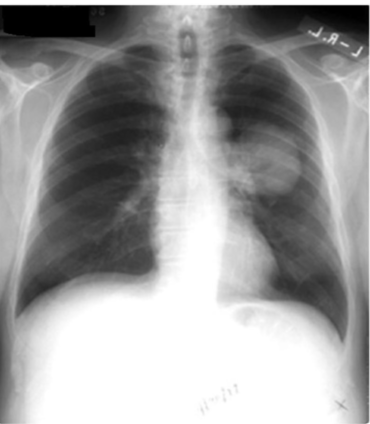

What is going on in these pictures. Whats the dx?

Left pic: normal

Right pic: COPD

whats the dx for these pics?

Left: normal

Right: pneumonia